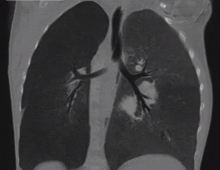

This 2-year-old girl was evaluated for a recurrent respiratory tract infection and palpitations. She was further evaluated and diagnosed with a large secundum atrial septal defect (ASD) with dilated right atrium (RA) and right ventricle. However, the left pulmonary artery was not visible on the echocardiogram. A chest computed tomography scan showed that the left pulmonary artery (LPA) arose from the right pulmonary artery (RPA). The LPA traveled between the trachea and esophagus, causing a vascular sling and also compressing the left main bronchial stump. There was no evidence of tracheal stenosis or complete tracheal ring. In view of the vascular sling, she was taken up for surgery.